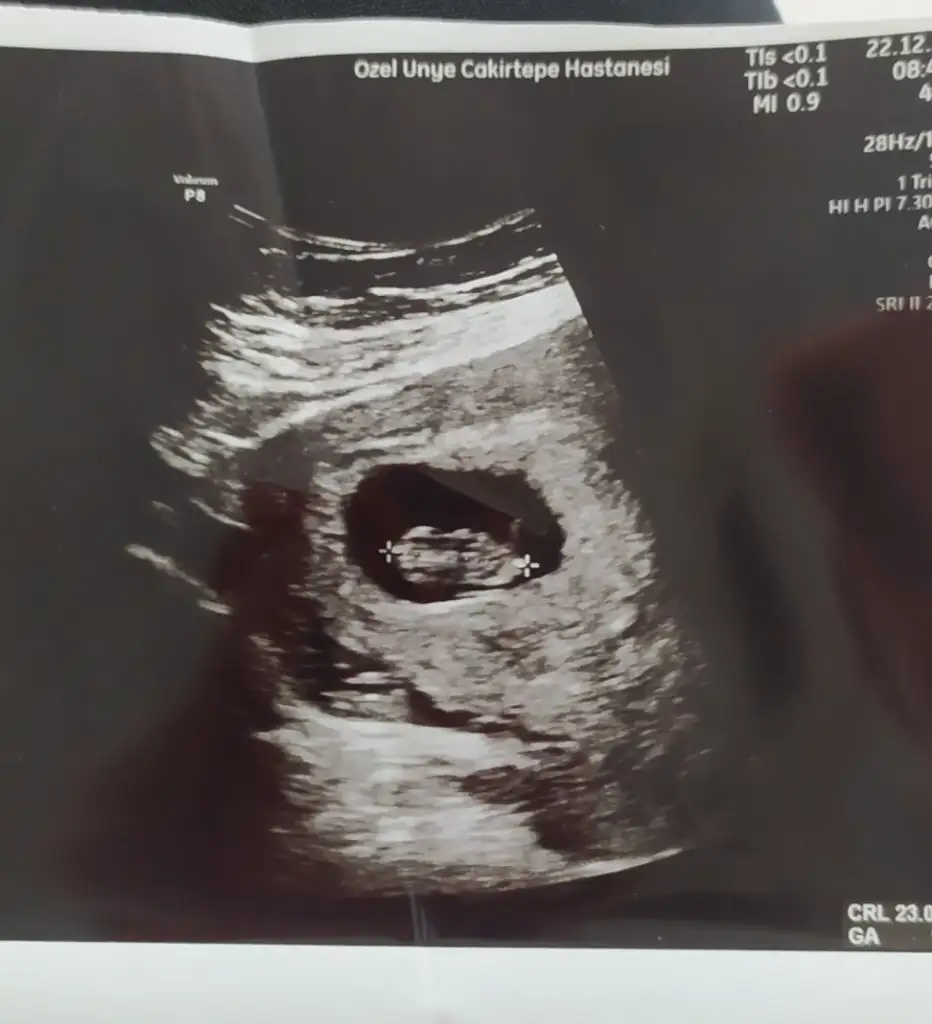

Sizin cinsiyet ne dediler13+6 nubu kız gibi ama bacak arasında da çıkıntı var gibi sizin tahmininiz nedir

12 haftalik sizce nedir cinsiyeti

Kız gibi duruyo ama net diyemiyorum küçük dahaSizce de kız mı acaba, sağlıkla gelsin inşallah. Yarın birde devlet hastanesine gideceğim, o zaman bir ultrason fotosu daha olur gerçi.

Kiz bence erkek olunca nub daha dik oluyorMerhaba, rica etsem cinsiyet tahmini yapabilirmisiniz? Ben araştırdım kız gibi ama nub yukarıda bakıyor sanki emin olamadım.